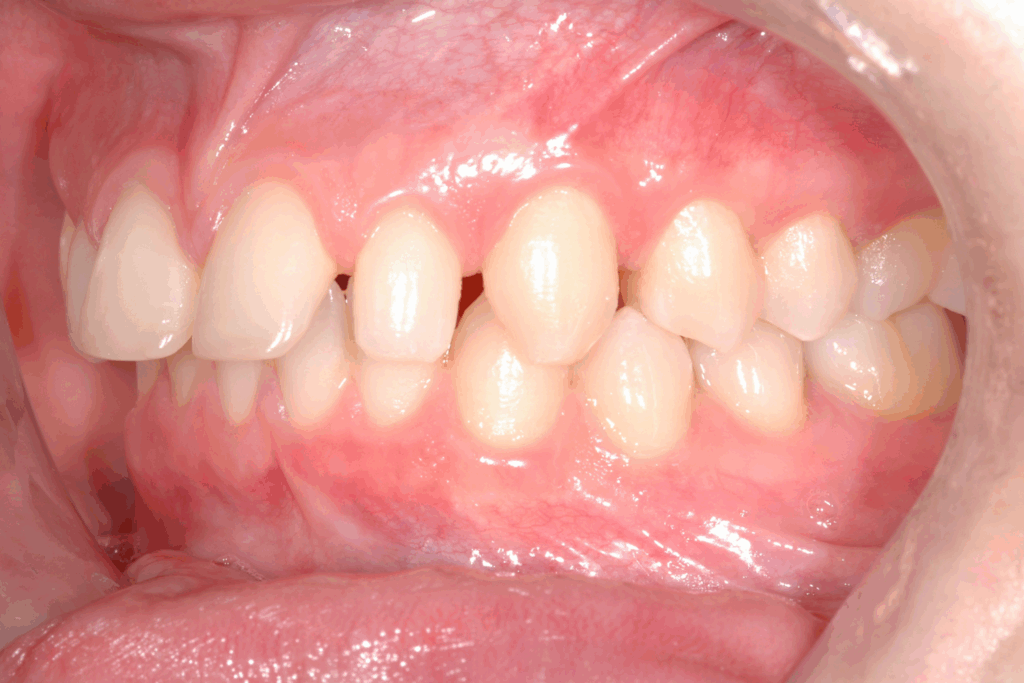

La prima fase del trattamento è stata un’analisi approfondita. Durante il check-up, abbiamo confermato la diagnosi di agenesia dei secondi molari permanenti inferiori, una condizione congenita che lascia spazi vuoti nell’arcata. Abbiamo inoltre rilevato che gli incisivi superiori erano di dimensioni ridotte rispetto al resto dei denti e che la paziente presentava un morso profondo, con gli incisivi superiori che coprivano eccessivamente quelli inferiori. Questa valutazione completa ci ha permesso di creare un piano di trattamento personalizzato e preciso, tenendo conto di tutte le problematiche presenti.

Per affrontare le sfide del caso, abbiamo optato per l’utilizzo di allineatori trasparenti. Questo tipo di trattamento è stato scelto per la sua efficacia nel muovere i denti in modo preciso e graduale, ma anche per la sua discrezione, fondamentale per una paziente in età scolare. Il piano di trattamento ha previsto una serie di allineatori personalizzati, che la paziente doveva sostituire con il passare delle settimane.

- Chiusura degli spazi: gli allineatori sono stati programmati per spostare i denti posteriori e chiudere gli spazi vuoti lasciati dall’agenesia dei settimi, evitando la necessità di impianti o ponti.